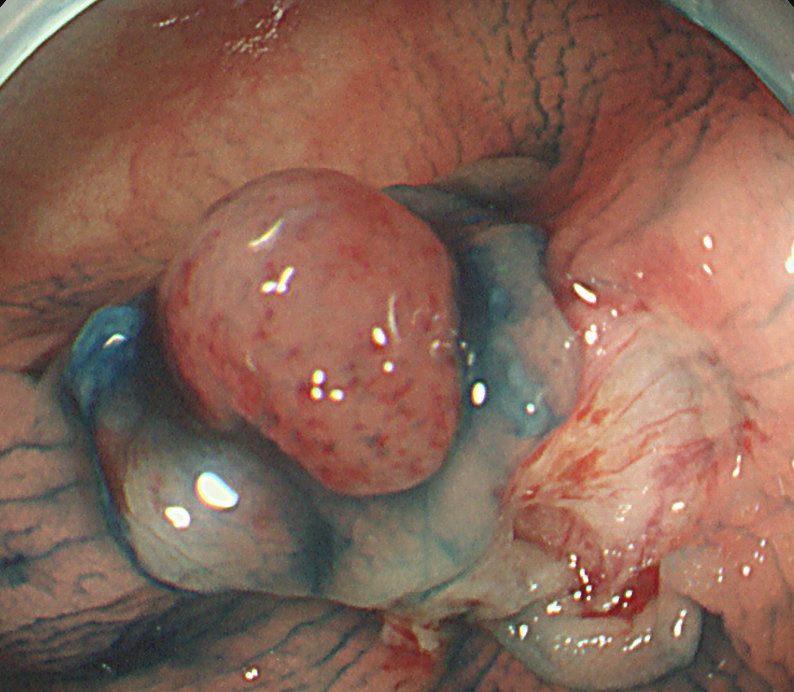

遺残・再発をゼロにするために「十分に周囲を大きく切除する必要」があります(「Extended Cold法」と呼ばれます)

Extended Cold法法で切除された検体は「目玉焼き」のようになります。「黄身」が病変で、「白み」が周囲の正常組織(余白、マージン)です。

腫瘍の取り残しを防ぐために「白み(余白)の大きな目玉焼き」にすることが、最大のポイントです。